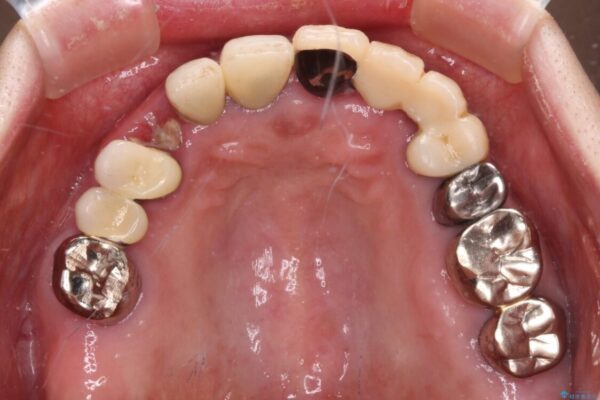

上顎犬歯や下顎大臼歯は、必要なところはインプラントを埋入することとしました。

クラウンが不適合であったり、根管治療の必要なほどの痛みのある歯であったり、見た目の気になる前歯などをオールセラミッククラウンに補綴治療を行うこととしました。

治療途中

• 前歯をきれいにしたい インプラントや部分矯正を用いた総合歯科治療 治療途中画像